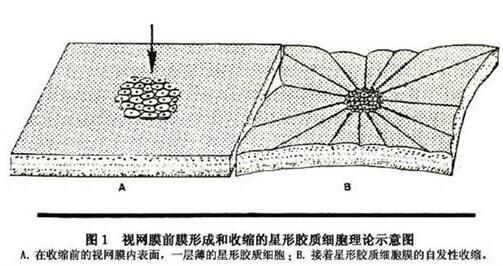

黄斑前膜